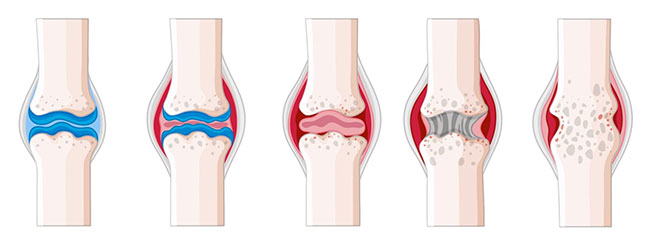

тя ми постави диагноза вторичен

остеоартрит с

усложнения. Честно казано, не разбирах какво точно казва. Обясни

приемам хапчета, които насърчават възстановяването на хрущялната тъкан, и след

като прочетох

внимателно упътването научих, че те не възстановяват, а само насърчават. И това

е всичко! Върви си,